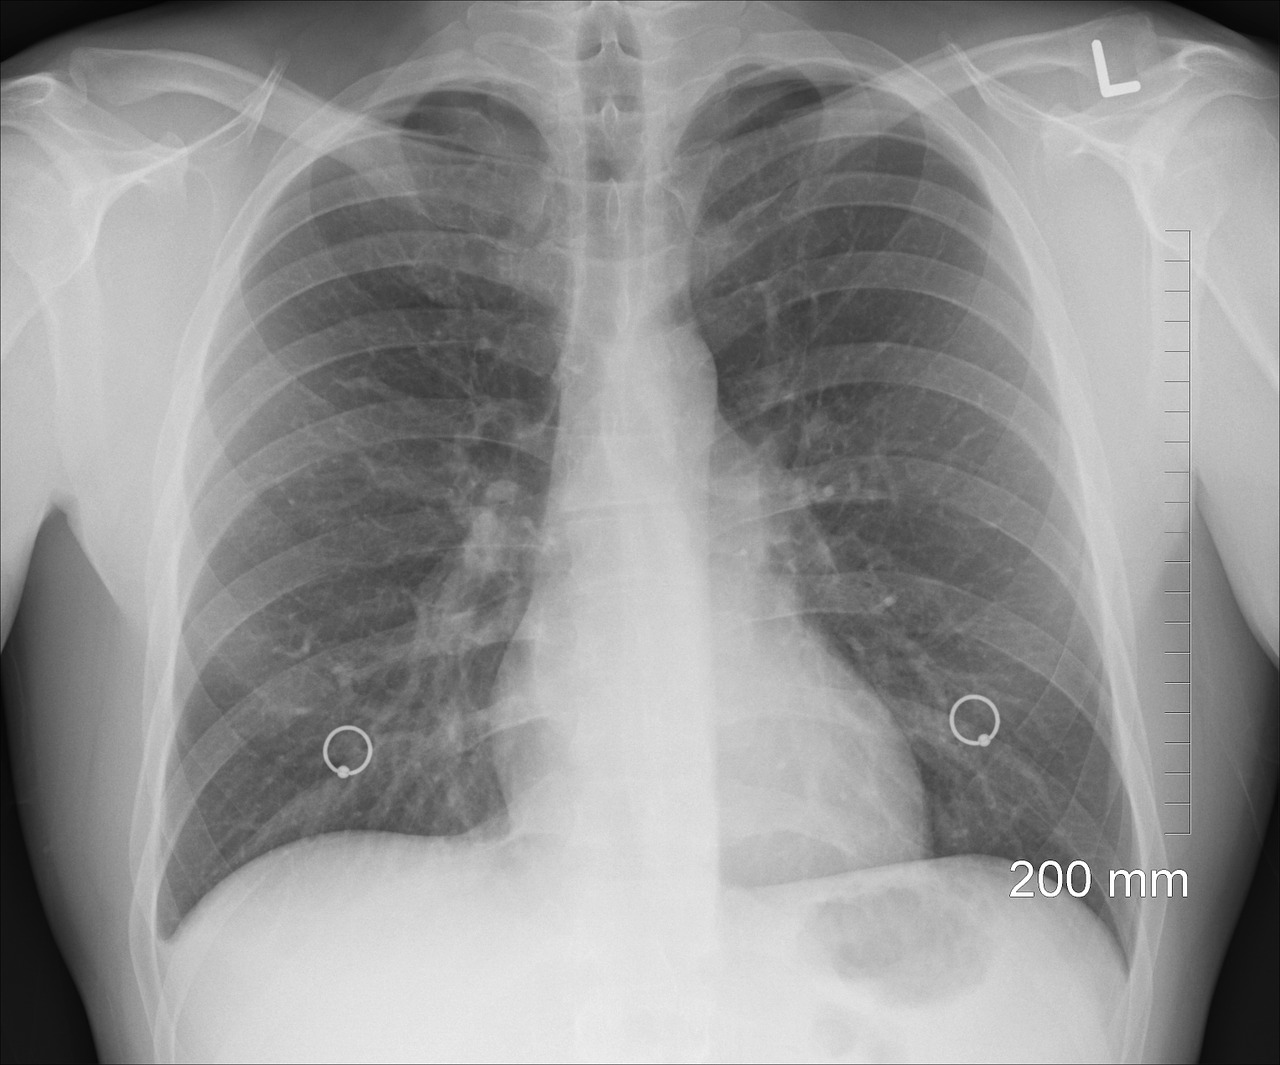

Zdiagnozowanie niektórych chorób płuc albo poważnych schorzeń układu oddechowego możliwe jest dopiero po wykonaniu szeregu specjalistycznych badań. Zwykle diagnoza obejmuje wywiad z pacjentem, badania laboratoryjne, prześwietlenie rentgenowskie klatki piersiowej oraz spirometrię. Spirometria jest badaniem czynnościowym układu oddechowego, krótko mówiąc – pomiarem oddychania.